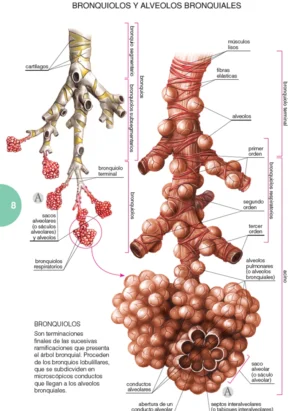

Un libro de la extensión de este no puede explicarlo todo sobre el tema. Pero sí aporta una cantidad más que suficiente de información para que tanto el profesional, como el paciente puedan encontrar en él todo aquello que constituye el núcleo fundamental de conocimientos sobre la enfermedad, además de un gran acopio de materiales complementarios, tanto de tipo ilustrativo como, sobre todo, práctico, que servirán eficientemente para conocer en su globalidad qué es la EPOC, cómo tratarla y la manera más adecuada para que el paciente pueda hacerle frente.